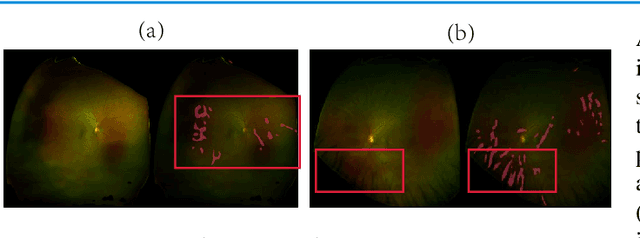

Abstract:Dermatologists often diagnose or rule out early melanoma by evaluating the follow-up dermoscopic images of skin lesions. However, existing algorithms for early melanoma diagnosis are developed using single time-point images of lesions. Ignoring the temporal, morphological changes of lesions can lead to misdiagnosis in borderline cases. In this study, we propose a framework for automated early melanoma diagnosis using sequential dermoscopic images. To this end, we construct our method in three steps. First, we align sequential dermoscopic images of skin lesions using estimated Euclidean transformations, extract the lesion growth region by computing image differences among the consecutive images, and then propose a spatio-temporal network to capture the dermoscopic changes from aligned lesion images and the corresponding difference images. Finally, we develop an early diagnosis module to compute probability scores of malignancy for lesion images over time. We collected 179 serial dermoscopic imaging data from 122 patients to verify our method. Extensive experiments show that the proposed model outperforms other commonly used sequence models. We also compared the diagnostic results of our model with those of seven experienced dermatologists and five registrars. Our model achieved higher diagnostic accuracy than clinicians (63.69% vs. 54.33%, respectively) and provided an earlier diagnosis of melanoma (60.7% vs. 32.7% of melanoma correctly diagnosed on the first follow-up images). These results demonstrate that our model can be used to identify melanocytic lesions that are at high-risk of malignant transformation earlier in the disease process and thereby redefine what is possible in the early detection of melanoma.